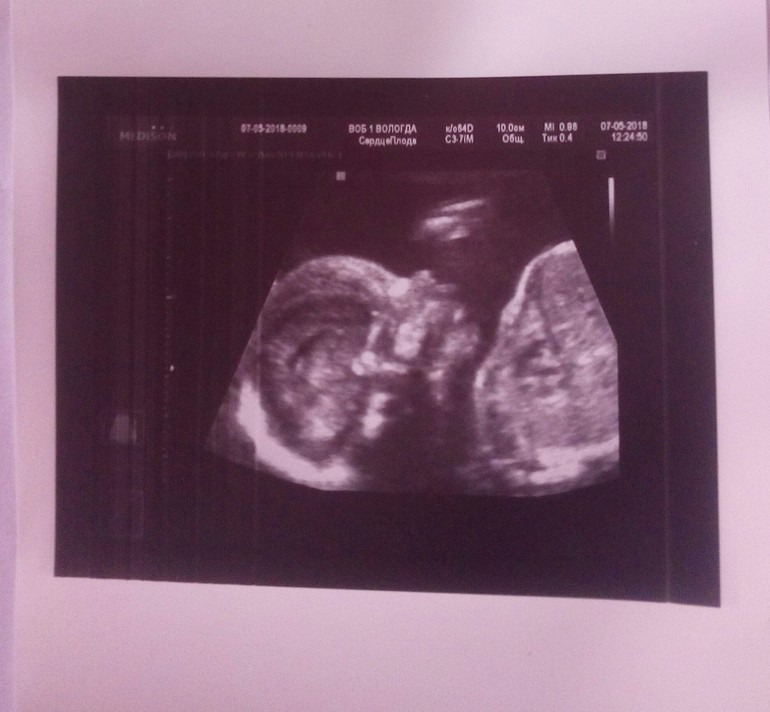

Рушана в Благополучная беременность 8 лет УЗИ УЗИ, КТГ, доплер 2 УЗИ пройдено...девчуля наша неугомонная.. всё УЗИ показывала кулачки.и перевернулась в головное.. Посмотрите еще 20 записей на эту тему Отменить Ответить Елена 14.05.2018 Ответить Рушана Спасибо !!! 15.05.2018 Ответить Dasa Ой, у меня тоже с ручкой :) Правда до сих пор сидит на попке!) 08.05.2018 Ответить Анна Ох, у меня до 30 недель туда сюда. То головой то попой вниз. Атас. 08.05.2018 Ответить Рушана Ну да..врач сказал ещё может 10 раз перевернуться ) 08.05.2018 Ответить AngelaMom какие они все таки разные даже на узи снимках))поздравляю с девочкой) 07.05.2018 Ответить Дарья Красотуля!)) 07.05.2018 Ответить Успокойте меня кто-то. ЧЛС почек плода Симфизит Чаты Беременных Выберите чат: Январята-2026 Февралята-2026 Мартята-2026 Апрелята-2026 Майчата-2026 Июнята-2026 Июлята-2026 Августята-2026